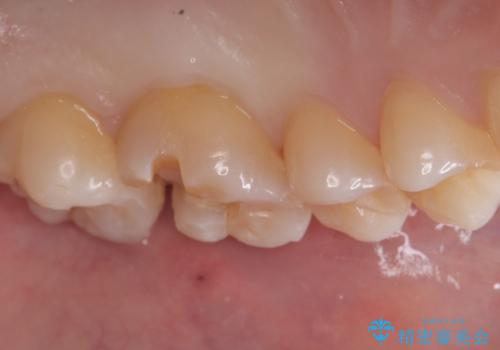

- 主訴:舌で触ったら歯に穴が空いていた。しみたりはしていない。

左上6番目の歯の噛む面に穴が空いていました。穴自体は小さいものでしたが、歯の中で虫歯が広がっていることが確認でき、虫歯の大きさを考慮しインレーでのやり替えとなりました。

咬合面に穴が空き、歯の中でう蝕が広がっていました。この歯が過去に咬合面う蝕を経験しCR修復を受けていること、今回歯質とCRの境目からの二次う蝕になっていることを説明し、適合や材料安定性の良いセラミックインレーでのやり替えとなりました。